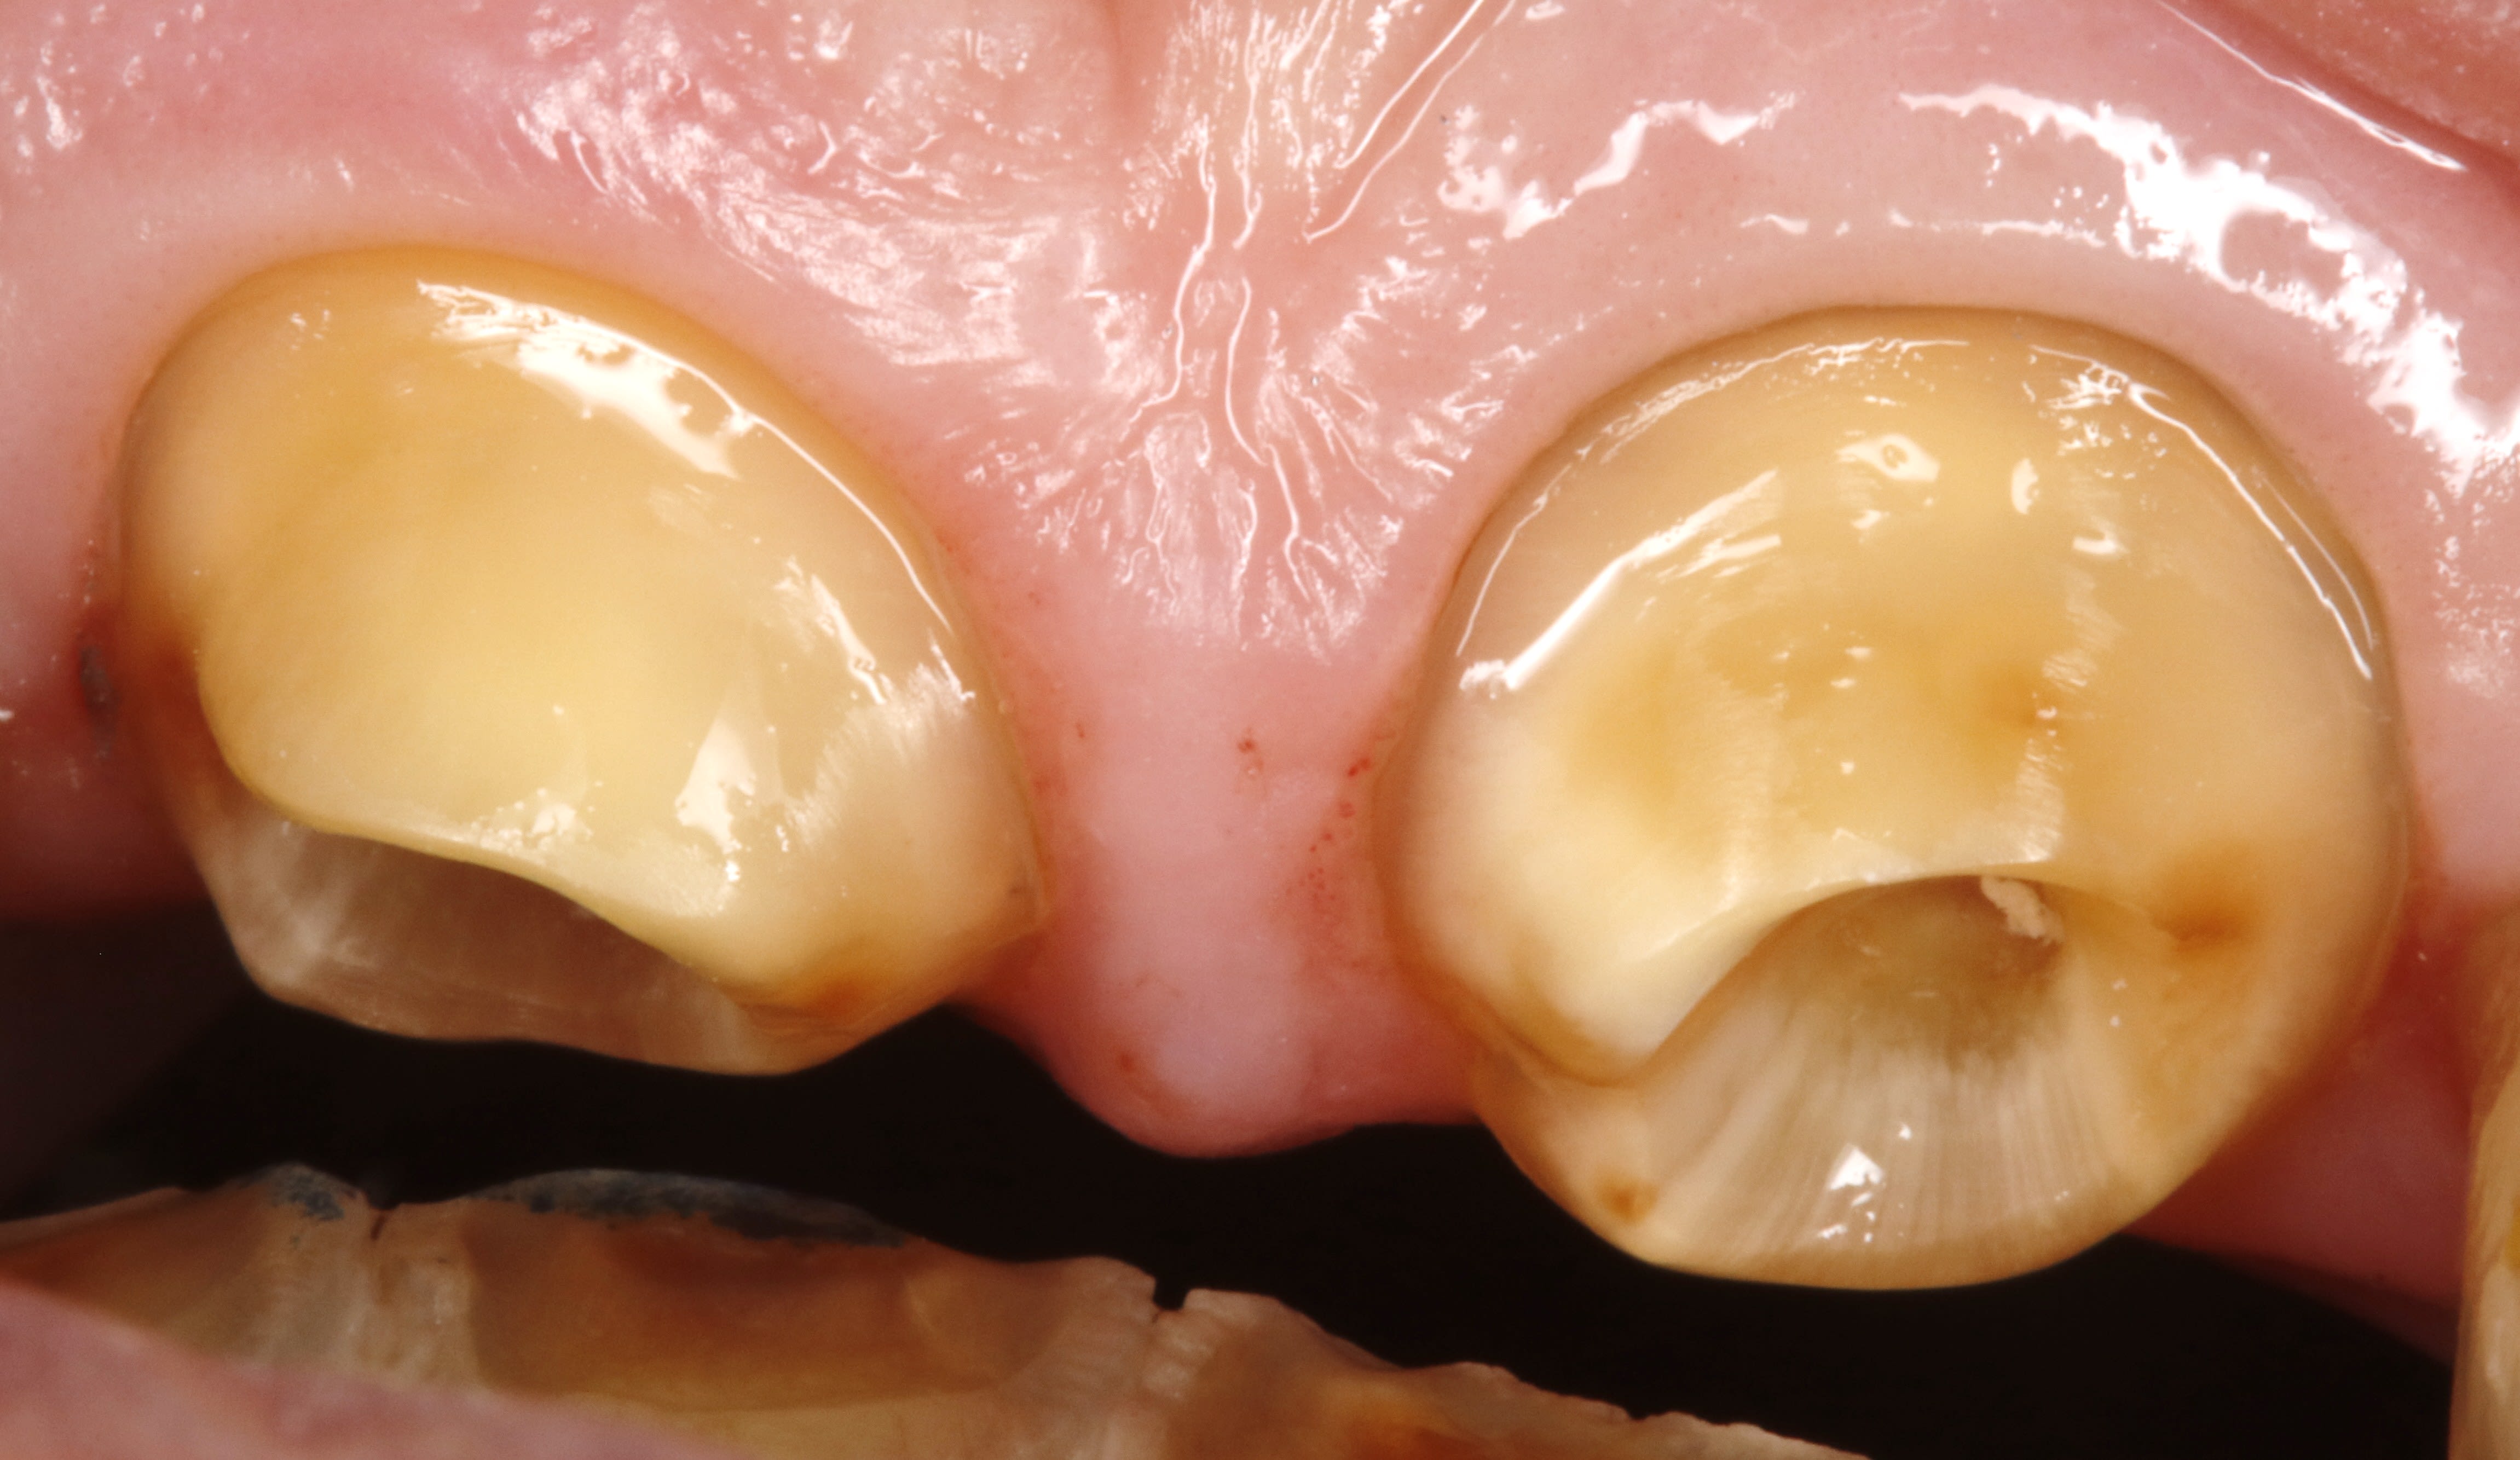

et là ç est le 1 er jour , le jour de l endo .

le but est de pretailler la dent en restant juxta .

en aucun cas ,il faut toucher la gencive le 1 ere séance . ( sauf s'il y a carie bien sur , mais ç est tres ponctuel ).

la seance d apres , alors que l on a pas touché la gencive , hein , et bien elle va se rétracter , pcq elle sera stimulée mecaniquement .

voilà , ce matin on est donc à 1 semaine .

on voit que la gencive ç est tassée .

je dis tasseé pcq on ne peut pas dire cicatrisée puisqu on ne l avait pas touché la semaine passée .

on peut mettre 1 fil , et meme se servir du chausse pied , ça ne saignera pas , ç est du beurre .

et on reprecise les limites à la grain fin .

donc voila la taille finie ce jour et comme bien sur ça ne saigne pas , je peux prendre l empreinte aujourd'hui pour une zolie richmond support de crochet .